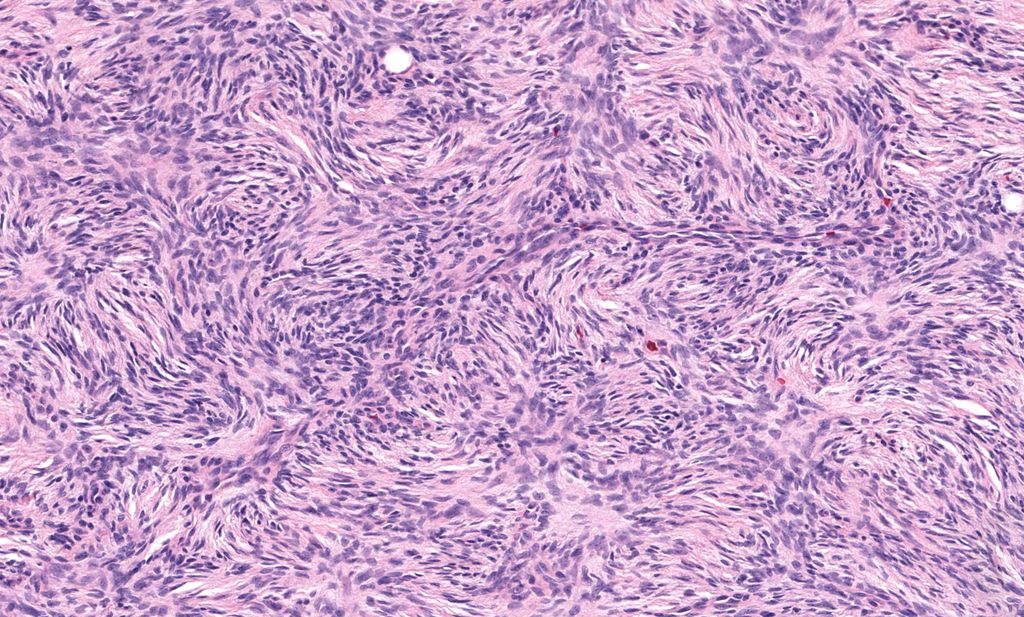

What is the name for this spindle cell pattern? What tumor is it classically seen in? Answer ✅ youtu.be/3u7uL9asZDg?si… More info: kikoxp.com/posts/10744 WSI digital slides: kikoxp.com/posts/6818 #pathology #pathologists #pathTwitter #dermpath #dermatology #dermtwitter

What is the name for this spindle cell pattern? What tumor is it classically seen in?

Answer ✅ youtu.be/3u7uL9asZDg?si…

More info: kikoxp.com/posts/10744

WSI digital slides: kikoxp.com/posts/6818